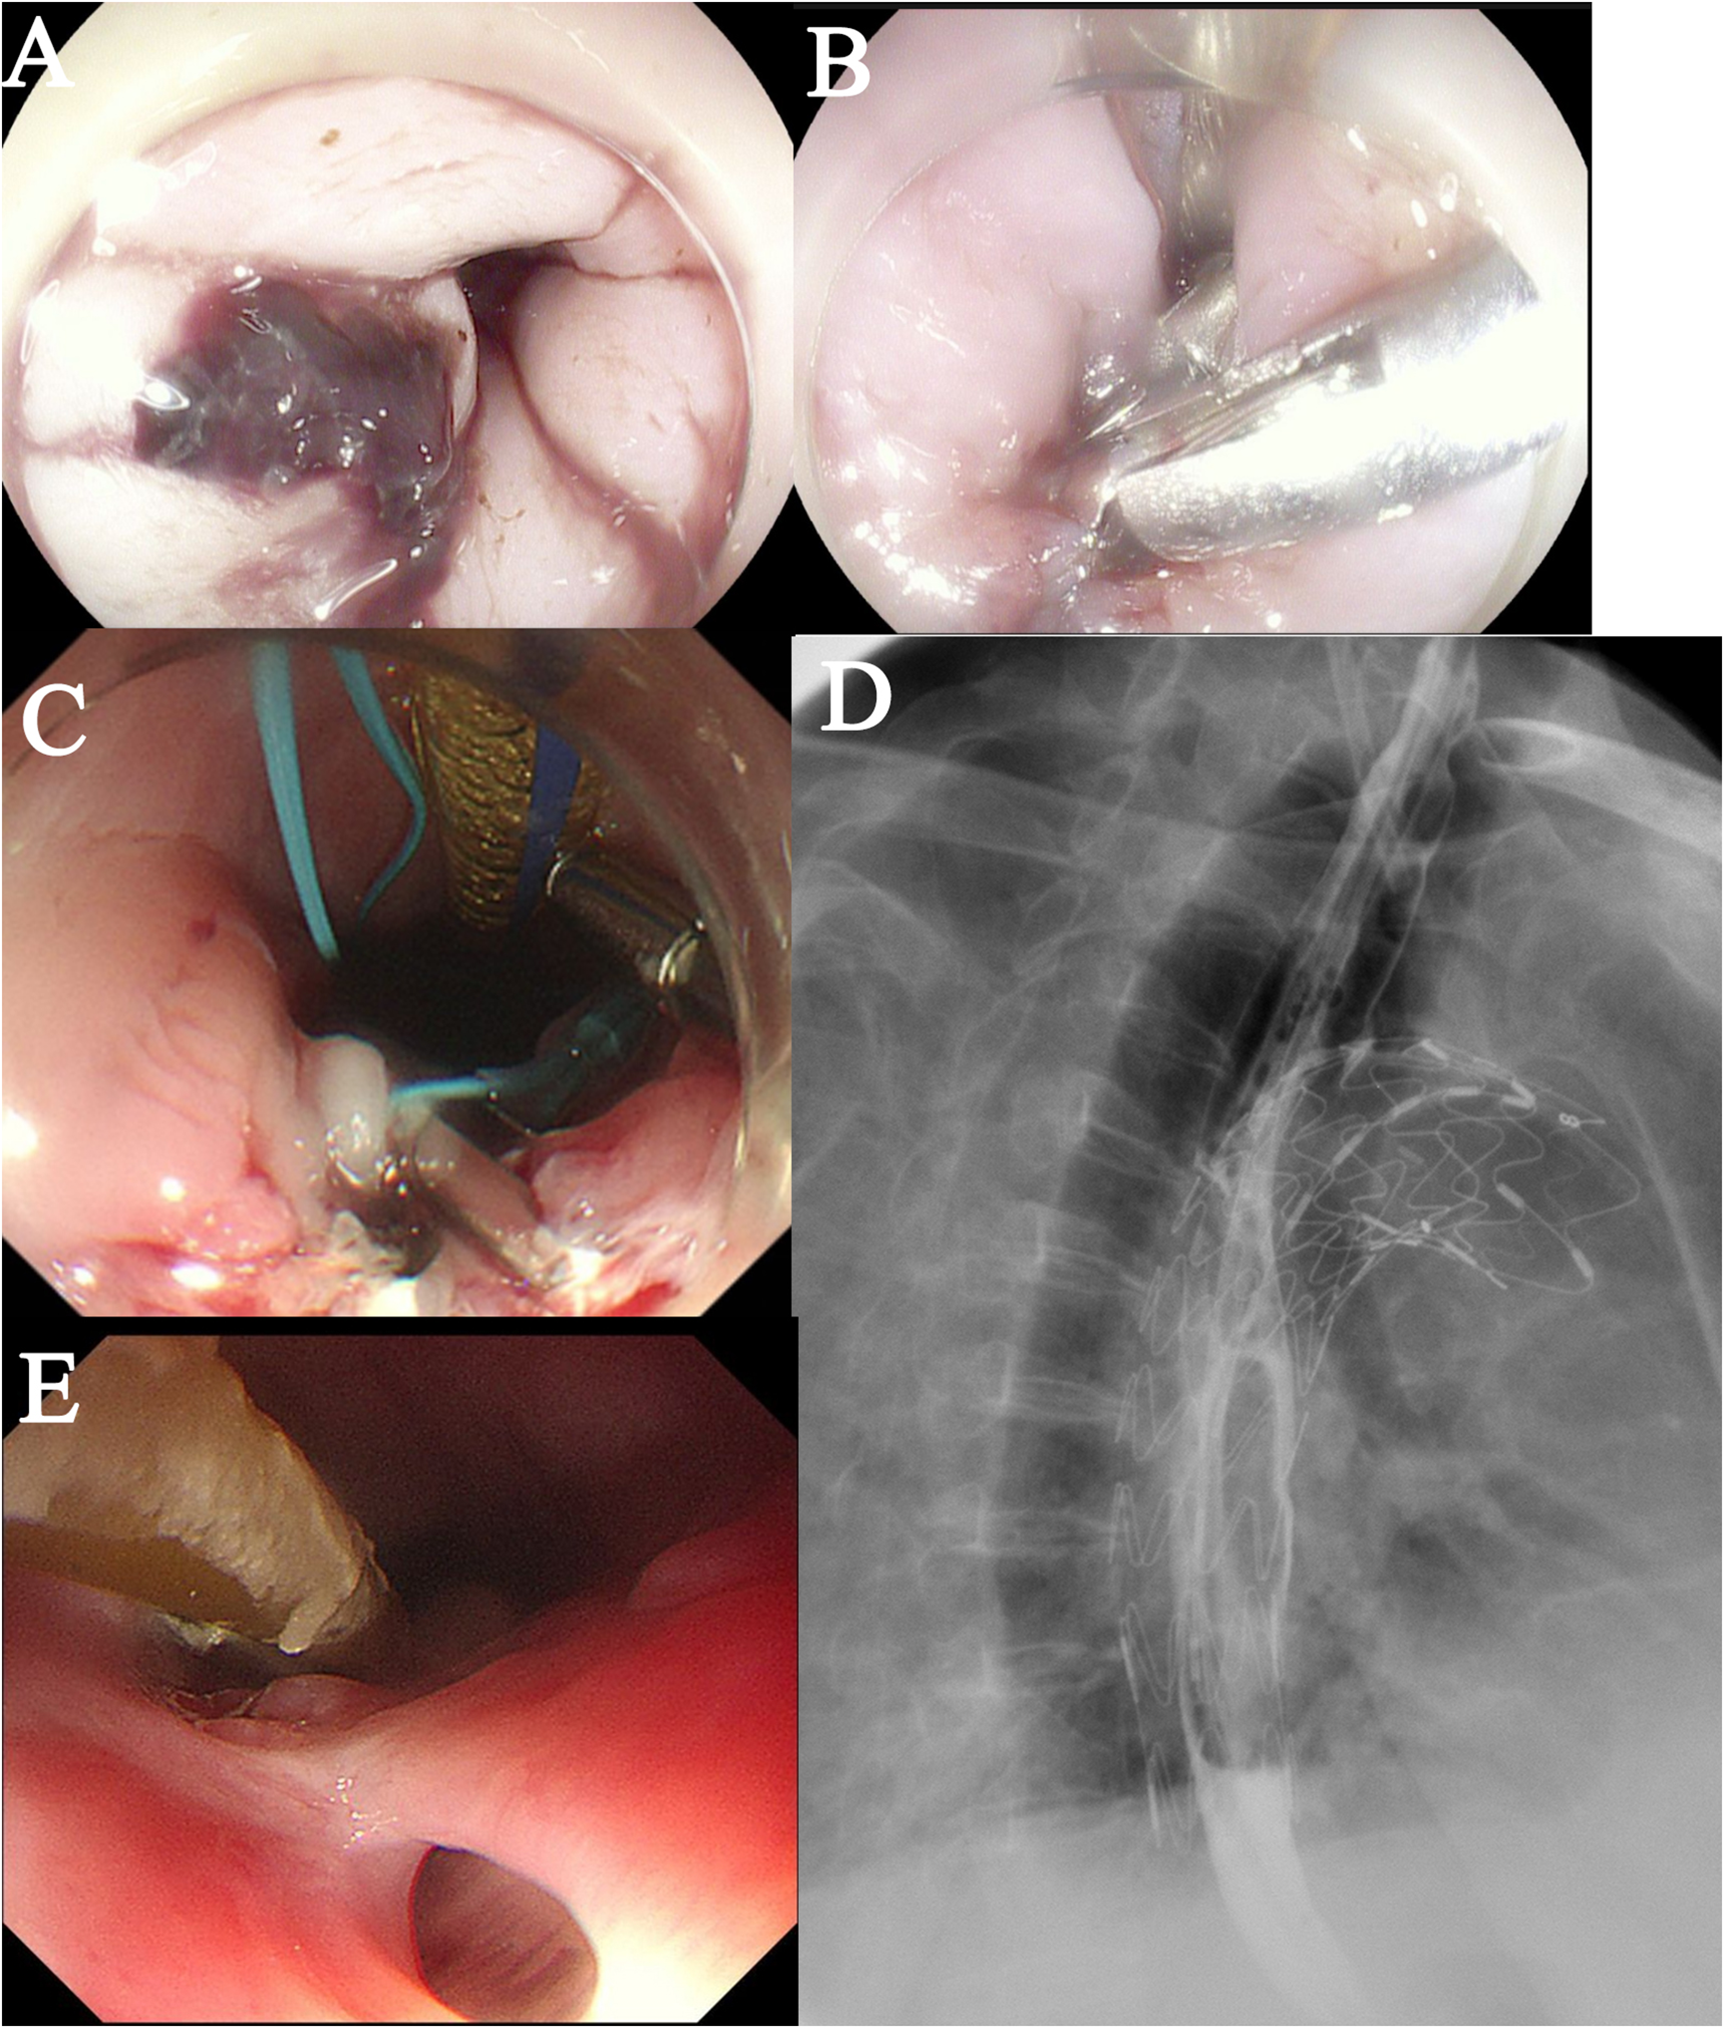

On Postoperative Day 2, gastroscopy revealed a 15 mm laceration in the esophagus approximately 20 cm from the incisors (Figure 3A). Given the patient's frail condition and financial constraints, the defect was closed using two titanium clips (Figure 3B). On Day 8, a repeat gastroscopy showed that the initial clips had dislodged. After debridement of the site, the laceration was re-closed with three titanium clips reinforced with a nylon loop (Figure 3C). Enteral nutrition via a nasojejunal tube was initiated on Day 9, with strict instructions to maintain nil-by-mouth status.

Figure 3

Postoperative esophageal evaluation. (A) A bleeding laceration (approximately 1.5 cm in length) is observed in the esophagus. (B) The defect was closed using endoscopic clipping. (C) The laceration was re-closed with three titanium clips reinforced with a nylon loop. (D) A barium esophagogram confirmed good esophageal integrity with no evidence of leakage. (E) A follow-up endoscopy showed an intact external esophageal wall.

Empirical antibiotic therapy with cefoperazone-sulbactam plus tinidazole was administered from Day 0 to Day 4. During this period, the patient's body temperature(T) fluctuated between 37.0°C and 37.5 °C, and the procalcitonin (PCT) level decreased from 6.202 ng/mL to 1.202 ng/mL (Normal value <0.05 ng/mL). The regimen was then escalated to piperacillin-tazobactam, after which the body temperature dropped below 37.0°C and the PCT level continued to decline. On Day 9, sputum culture identified ESBL-producing bacteria and Acinetobacter baumannii. Accordingly, the antibiotic therapy was changed to meropenem, and tinidazole was discontinued. On Day 16, sputum culture grew Pseudomonas aeruginosa, leading to the addition of moxifloxacin to the regimen, which was continued until discharge. A barium esophagogram performed on Day 15 confirmed good esophageal integrity with no evidence of leakage (Figure 3D). The patient was discharged on Day 29 in a stable condition (T:36.6°C, PCT: 0.022 ng/mL) and a chest CT showing no significant mediastinal infection.

The patient was discharged with instructions to continue anti-infective therapy at a local hospital and to avoid oral intake. On Day 40, a follow-up endoscopy at our hospital showed an intact external esophageal wall (Figure 3E). However, a sinus tract was found, debrided, and closed again with three titanium clips. The patient was advised to commence a liquid diet orally.